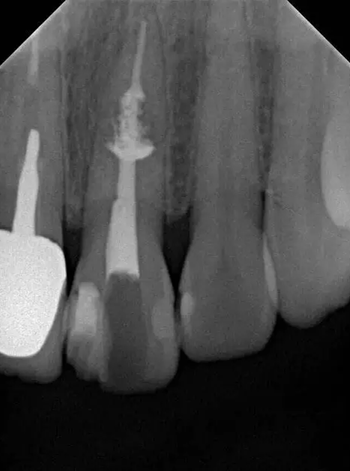

診斷:左上中切牙牙根內(nèi)吸收。治療計(jì)劃:左上中切牙根管治療,全冠修復(fù)。 治療過程:患者知情同意。使用含1/100,000腎上腺素的4%鹽酸阿替卡因(碧蘭麻,艾龍)局部浸潤(rùn)麻醉,橡皮障隔濕。去腐未盡露髓,露髓孔出血多。開髓,使用10#不銹鋼K銼(MANI,日本)探查根管,根管中段有鈣化物阻擋,不能達(dá)到牙根全長(zhǎng)(圖3A)。在顯微鏡下(Leica M400E,萊卡, 德國(guó)) 使用超聲尖(E1根管治療超聲尖,啄木鳥公司,中國(guó))通開,采用根管長(zhǎng)度測(cè)量?jī)x(Root ZX, Morita公司,日本)加診斷絲片法(圖1B)測(cè)量根管長(zhǎng)22 mm。使用控制扭矩馬達(dá)(X-smart,登士柏)和鎳鈦旋轉(zhuǎn)器械(Hero 642, Micromega)根管預(yù)備,根管預(yù)備過程中使用5.25%次氯酸鈉溶液沖洗。 根備完成后使用超聲蕩洗根管,5.25%次氯酸鈉溶液3 分鐘, 17% EDTA溶液1分鐘。干燥根管,使用螺旋充填器根管內(nèi)封氫氧化鈣糊,氧化鋅丁香油水門汀暫封。1周后患者復(fù)診,患者述無術(shù)后不適,檢查暫封完好,無叩痛,不松,牙齦無紅腫瘺管。使用橡皮障隔濕,去除暫封物,超聲蕩洗根管,5.25%次氯酸鈉溶液3 分鐘, 17% EDTA溶液1分鐘。干燥根管,牙膠尖(達(dá)雅鼎,中國(guó))和必蘭根充糊劑(Cortisomol, 艾龍公司,法國(guó))熱垂直加壓法根管充填。術(shù)后片顯示根充恰填,可見牙膠/糊劑被壓入鈣化物周圍和內(nèi)部縫隙內(nèi)